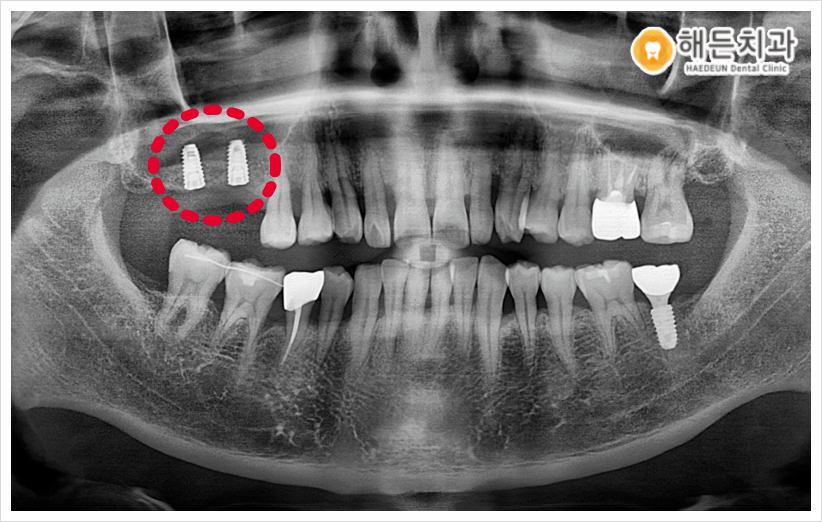

상악동 거상술을 통해 부족한 뼈를 보강하여 임플란트를 안정적으로 식립하였고, 임플란트 식립 후에 픽스처 주변으로 잇몸뼈가 부족한 부분에도 인공뼈를 이식해 드렸습니다.

인공뼈와 픽스쳐가 단단하게 유착될 때까지 충분히 기다린 후, 골 결합 정도를 수치로 확인할 수 있는 장비인 Osstell을 통해 식립이 안정적으로 잘 되었는지 확인한 뒤 최종 보철물까지 마무리 해드리기로 하였습니다!

이렇게 상악동 거상술을 동반한 임플란트 식립으로 환자분의 불편감을 해소시켜드린 사례를 소개해 드렸습니다. 🤗

상악동 거상술은 고도의 수술 테크닉을 요하며 환자분의 잔존 뼈의 두께와 양, 골질에 따라 치료 계획이 달라질 수 있기 때문에 수술 경험이 풍부한 의료진과 진행하는 것이 좋은데요.